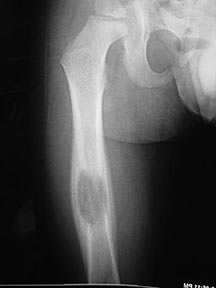

- May arise from any bone and any site within a bone (epiphyseal, metaphyseal, diaphyseal)

- Radiographically variable appearance: may appear benign (geographic) or malignant (permeative or moth eaten)

- Femur

- Curettage and bone grafting for long bones and weight bearing bones at risk for fracture